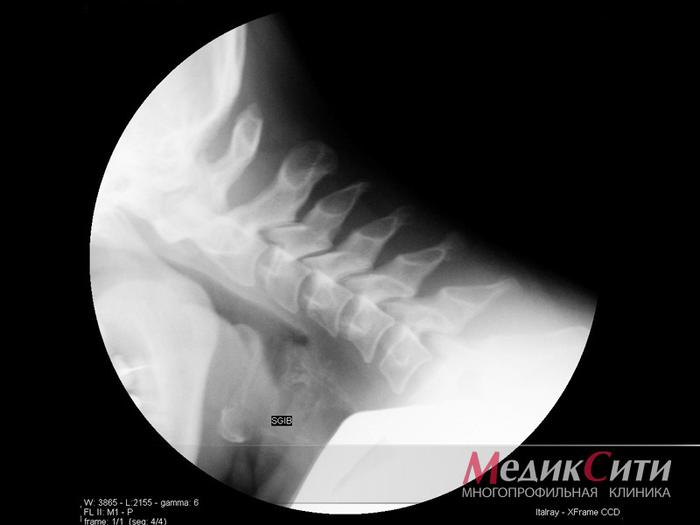

Рентгенография суставов на начальной стадии заболеваний не дает много информации. Но если у вас уже есть снимки, обязательно принесите пленки или диски. Бумажные распечатки не позволят детально оценить и правильно интерпретировать изображение. Несмотря на выводы заключения, ревматолог обязательно просматривает снимки сам!»

Рентген в МедикСити

Рентген шейного отдела позвоночника в МедикСити

Также полезные данные при заболеваниях соединительной ткани могут быть получены с помощью инструментальных исследований. Например, рентгенография костей и суставов позволит выявить наличие остеопороза, сужение суставных щелей, эрозию или асептические некрозы суставных поверхностей, а также дегенеративные изменения костной ткани. Ультразвуковые исследования, МРТ и КТ могут помочь в диагностике заболеваний внутренних органов и оценке характера и степени патологических изменений.